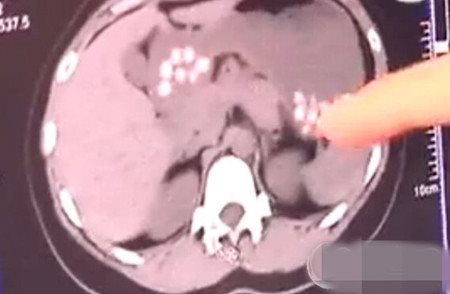

2015年10月,网友一张胃里有密密麻麻小白点的CT照片在朋友圈热传,记者前去采访时,山东青岛一名店主称珍珠奶茶里的珍珠是用皮鞋底、旧轮胎做的。